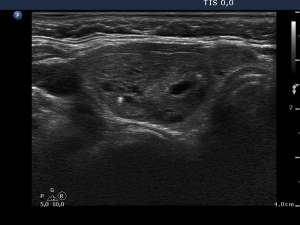

6 weeks after the last session (third row of images):

Clinical presentation: the patient had no complaints.

Hormonal investigation indicated euthyroidism (TSH 0.47 mIU/L, FT4 13.1 pM/L).

Ultrasonography: the nodule decreased significantly and became inhomogeneous.